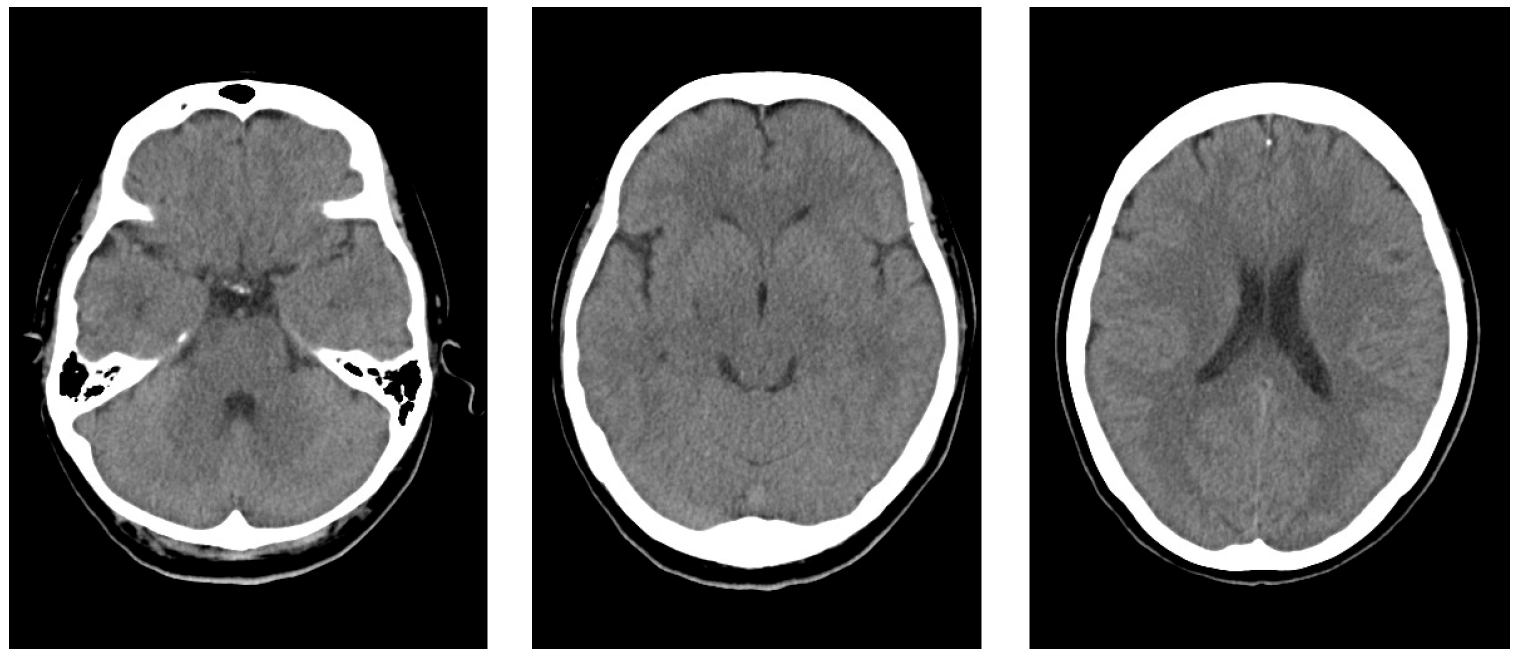

2. Case Report